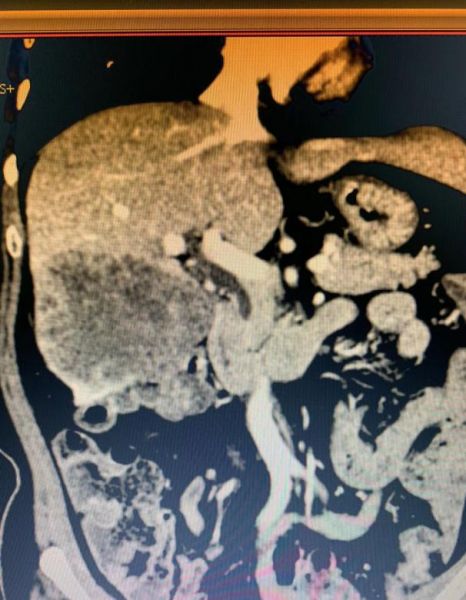

来自吉首的瞿女士,因腹痛、呕吐并肛门停止排气排便入住胃肠外科,经检查诊断为不完全性肠梗阻,经对症治疗后症状缓解。进一步完善CT检查发现肝脏一巨块性肿瘤,结肠镜检查提示乙状结肠占位,考虑结肠癌并肝转移,申请肝胆外二科会诊后转入该科。肝胆外二科主任姚本能主任医师将患者的病情在科内提出讨论,肝胆外科大主任宋新、肝胆外二科周后平副主任医师等详细询问患者病史,认真查体并审阅影像学资料后,认为肝脏肿块巨大,来源结肠可能,并提请院内多学科会诊,进行了全面讨论。因其它部位未见明显肿瘤转移,参考结肠癌肝转移诊疗指南,会诊认为患者具备手术治疗指征,将病情及治疗方案详细告知家属后,取得了患方的充分理解和信任,决定由肝胆外科、肛肠外科联合为患者实施手术治疗,具体手术方式拟定右半肝切除,序贯结肠部分切除,淋巴结清扫,乙状结肠造瘘术。

术前影像学资料